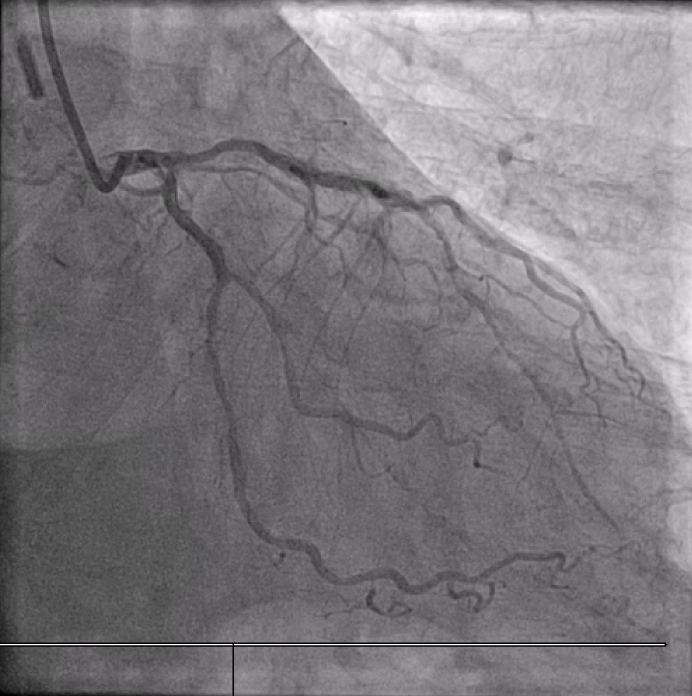

Distal LM intermediate disease, significant proximal LAD ISR, significant mid LCx stenosis. Diffuse high-grade RCA disease (proximal to distal into RPDA). Calcific and angulated proximal RPDA.

In view of severe left ventricular dysfunction, a 40cc IABP was inserted via the right common femoral artery for mechanical circulatory support during PCI. A 6Fr AL1 guide catheter was advanced via the right radial artery to selectively cannulate the right coronary artery (RCA). A Runthrough NS coronary guidewire was advanced into the distal R-PDA. Balloon angioplasty was performed from RPDA back to proximal RCA using a 2.5x15mm Sapphire3 NC balloon to 12atm. A Boston Scientific Opticross HD 60MHz IVUS catheter was advanced into the distal RPDA and intravascular imaging performed. Unfortunately, upon completion of the pullback run, the IVUS catheter could not be withdrawn. The IVUS catheter was stuck on the calcific and angulated segment in the proximal RPDA. Despite use of focused force technique, parallel ballooning, the IVUS catheter could not be withdrawn. During the attempts, the IVUS catheter inadvertently broke, leaving a short segment of the catheter in the RPDA. Check angiography showed no flow impairment. Thus, proximal to mid RCA was stented using a 3.0x38mm DES and a 3.5x48mm DES. Due to long procedural time, decision made to stage further PCI to the next day. The following day, PCI to LAD was performed uneventfully. The RCA was cannulated using a 7Fr AL2 guide catheter via right radial artery. A Sion Blue ES guidewire was advanced into the RPDA. A 6Fr Liquid guide extension catheter was advanced across the stented segments. A 3.2Fr EnSnare used to withdraw IVUS.